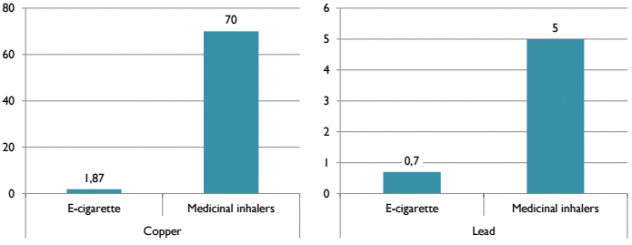

Однако эти значения довольно незначительны. Для сравнения, Доктор Фарсалинос сопоставил их содержание с разрешимым в медицине порогом для медицинских ингаляторов:

- Медь и свинец